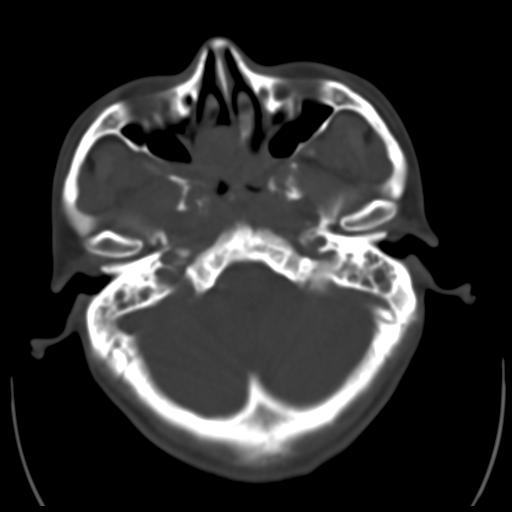

35m 鼻子时不时流血,头及右侧面部痛,颈部淋巴结未见明显大

软组织窗

骨窗

考虑鼻咽癌侵犯颅底并突入右侧鼻腔;双侧中耳乳突炎。

蝶窦,后组筛窦及鼻咽部团块状软组织影,骨壁破坏,病变较广泛。考虑恶性肉芽肿。建议活检。

颅底骨质明显破坏 支持鼻咽癌 但病灶的边缘毛糙 不能除外炎性

考虑中线肉芽肿(鼻硬结病),次之tb或真菌感染性肉芽肿,病变形态不像肿瘤,建议增强及活检。